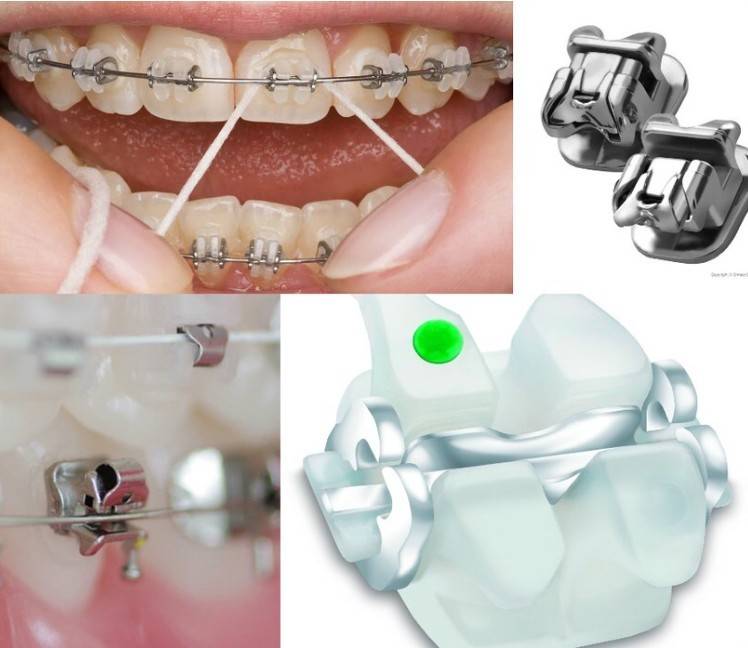

Лигатурные и самолигирующиеся системы

Лигатуры – это дополнительные элементы брекет-системы, которые удерживают дугу в пазу замочка. На начальном этапе лечения в качестве лигатур используются кусочки тонкой проволоки. Затем они заменяются на резинки. Основное назначение лигатур – обеспечение движения замочков вслед за изменяющейся формой дуги. Проволока фиксирует брекеты очень жестко, что часто приводит к неравномерной нагрузке на зубы. В связи с этим могут появиться ноющие боли, которые с трудом может переносить взрослый, не то, что ребенок. Резиночки прокрашиваются пишментами из пищевых продуктов и напитков, что требует их регулярной замены.

В самолигирующихся системах замочки имеют специальную клипсу, которая фиксирует дугу. Соединение с помощью клипсы не такое жесткое, как с помощью проволочной лигатуры. По мере смещения зубов замочки могут в небольших пределах смещаться относительно силовой дуги, что позволяет распределять нагрузку на зубочелюстную систему более равномерно.

Нельзя сказать однозначно, какая из систем лучше. Каждая из них отлично справляется с задачей устранения дефектов зубных рядов. Сроки лечения не зависят от типа используемой конструкции. Пациенту придется посещать стоматолога для коррекции системы примерно с одинаковой частотой. Безлигатурные системы изготавливаются из самых разных материалов, что позволяет «поиграть» с формой и цветом. В лигатурных резиночки могут быть самых разных цветов, что при желании позволяет превратить ортодонтическую конструкцию в стильный аксессуар.

Уход за брекетами

Для того, чтобы ежедневно очищать зубы и конструкцию от загрязнений, придется приобрести сразу несколько специальных устройств:

ортодонтическая зубная щетка благодаря особой форме и более мягкой щетине более тщательно очищает зубы без риска отклеивания замочков;

небольшие ершики, головки которых помещаются между дугой и поверхностью зубов;

зубная нить;

специальная зубная паста и ополаскиватель, сдерживающий размножение бактерий в полости рта после чистки;

ирригатор, специальное устройство, позволяющее вычистить налет из мест, куда щетка и ершики не могут достать.